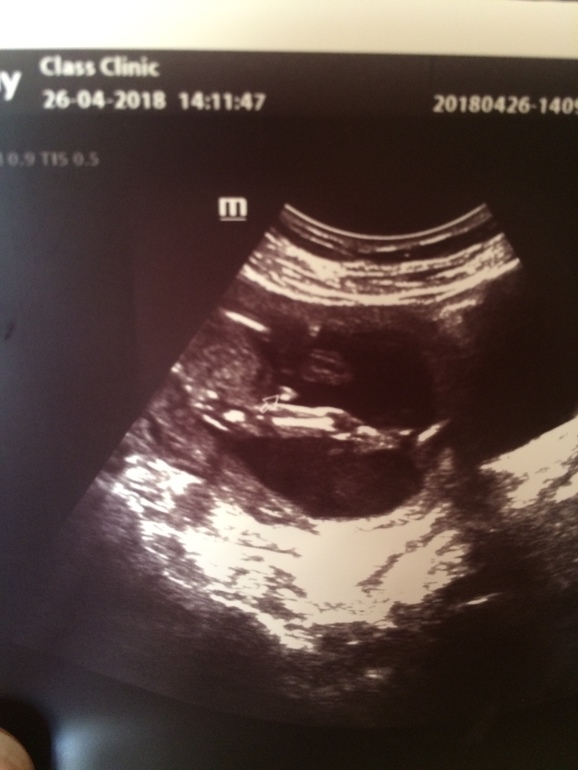

Вопросы про УЗИ, обследования и анализы: что, где, как, когда?Девочки, посмотрите пожалуйста фото с УЗИ моё. Это ведь точно мальчик? Не половой бугорок? Просто я не думала, что в 14 недель может быть так уже видно достоинство)))

меня запутали на УЗИ. Когда смотрели вид снизу, то там ничего не торчит, на вид как кофейное зёрнышко, а вот сбоку такой вид)) может у кого также было, что с разных ракурсов по-разному

Я бы ориентировалась на вид снизу. С третьей дочкой мне «писюнчик» фоткали, как на Вашем фото в 14 недель, даже найти могу, а снизу типа не видно было. Потом оказалось, что бугорок не доформирован был и это девочка. В этот раз только снизу смотрели, там уже без вариантов, что бугорок, это мужские подовые органы.